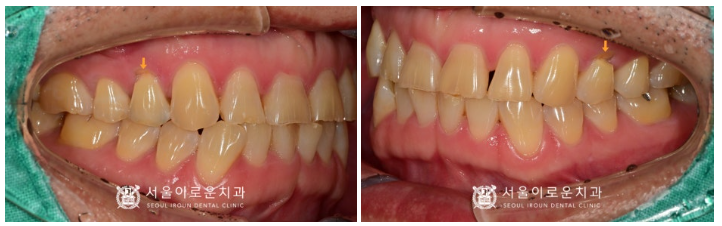

구강 내를 꼼꼼하게 확인해 보았더니

위턱 양측 첫 번째 작은 어금니(#14,24)의

치아 옆면이 쐐기 모양으로 패어있는

치경부 마모증이 관찰되었습니다.

환.자분께서도

위턱 양측 첫 번째 작은 어금니(#14,24)에서

차가운 자극과 바람에

매우 민감하게 반응하셨는데요.

더불어 위턱에 시려 하셨던

양측 첫 번째 작은 어금니(#14,24)의

치경부 마모증 부위도

환.자분의 치아 색상과

유사한 색의 레진으로

깔끔하게 수복을 도와드렸는데요.

치료를 받은 치아인지 아닌지 모를 정도로

너무 자연스럽지 않나요?

💛 전 > 후 💛

(2024.03.02ㅡ>2024.04.03)